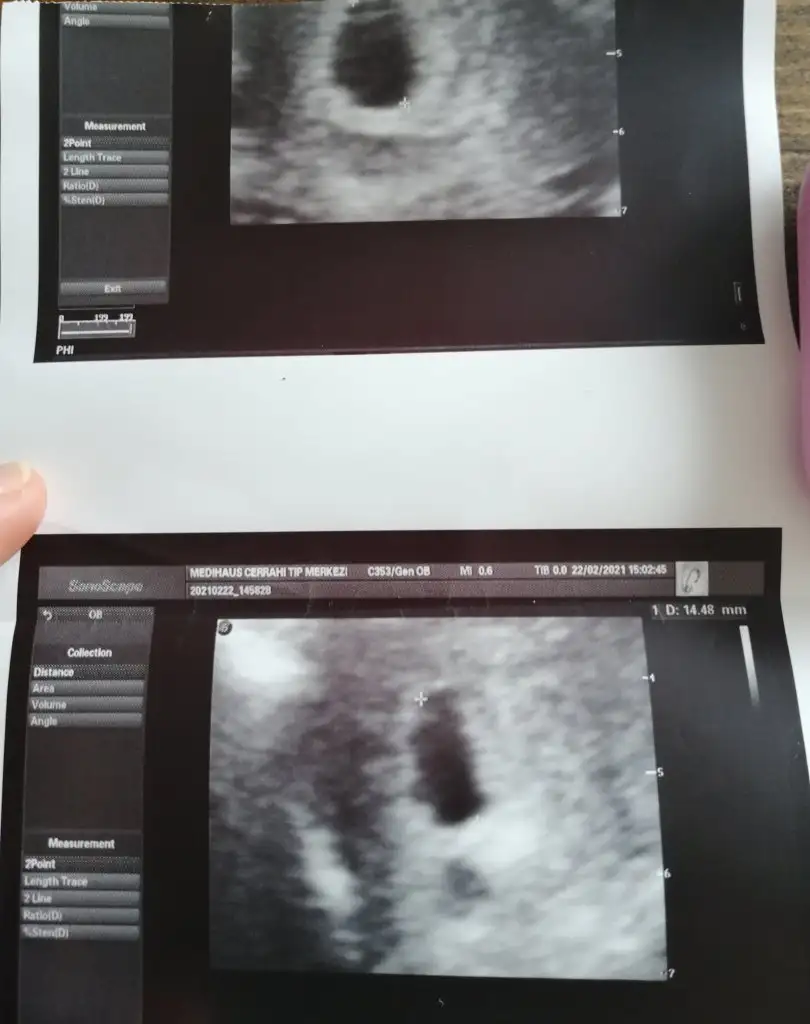

Benimde tam 2 kat olarak artmadı. 6 haftadan sonra 4 günde iki kat bile yükselmedi şuan 9. Haftadayım ve kalp atışını da duyduk şükür. Doktoruma söylediğimde her zaman kitaptaki gibi olmuyor dediKizlar 6+2 hamileyim kese görünmemişti 18 subatta 3800 cıktı beta bugun 25 subat 10.000 kese minik ama cok net birşey söylemiyorlar kanamam oldu cok az hastanedeyim 10.000 cok mu az artis lütfen fikirlerinize ihtiyacım var dr ameliyattaymış çıkmasını bekliyorum

Ben de 6+2 yim karindan görünmedi vajinal bakarak 5.6mm kese gördü ama ici boş bebek görünmedi kanama alanli minik bir kese bana da haftaya gel gelişmemişse belli olur alıcaz dedi rabbim mucizesini gostersin inşallah hepimizeMerhaba benimde bugün 7+1di ama karından göremedik vajinal baktırmadım boş gebelik yada daha küçük olduğu için görünmedi doktor sizede mi öyle denildi vajinada baktırdınız